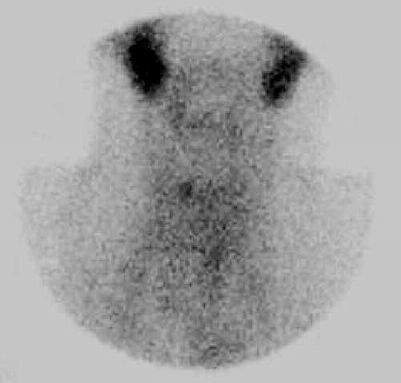

3. Scintigrafické vyšetření s 99mTctechnecistanem objektivizuje funkčnost reziduální tkáně štítné žlázy.

Ložisko akumulující technecistan v lůžku pravého laloku štítné žlázy.